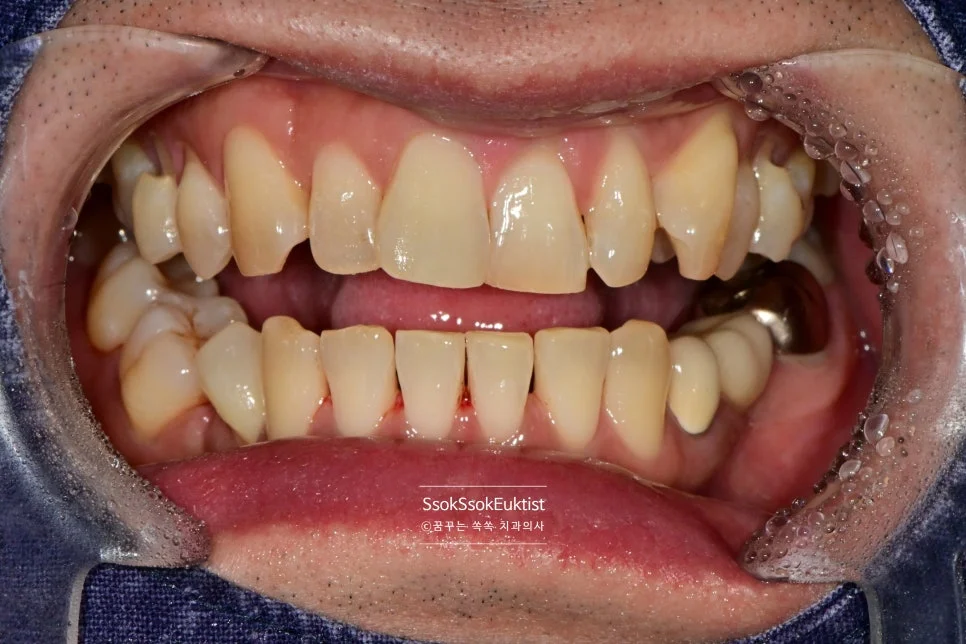

레진 치료 전 — V자 형태의 치경부 마모증

치아의 목 부분이 패여져 있는 모습입니다. 형태를 보면 U자라기보다는 V자에 가깝고, 즉 강한 교합력에 의해 치아 목 부분이 패였네요.